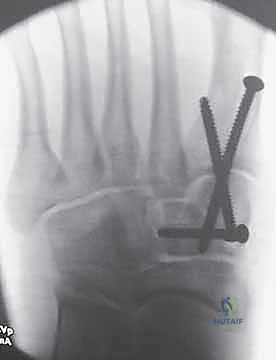

1. الرد المفتوح والتثبيت الداخلي (ORIF - Open Reduction and Internal Fixation)

هذا هو الإجراء الكلاسيكي والأكثر شيوعاً. يهدف إلى إعادة العظام إلى مكانها الطبيعي (الرد) وتثبيتها باستخدام معدات طبية (مسامير، شرائح، أو أسلاك) حتى تلتئم الأربطة والعظام.

خطوات العملية:

1. التخدير: يتم إجراء الجراحة تحت التخدير الموضعي (النصفي) أو العام.

2. الشق الجراحي: يقوم الدكتور هطيف بعمل شق جراحي دقيق (أو شقين) على ظهر القدم للوصول إلى المفاصل المصابة، مع الحرص الشديد على حماية الأعصاب والأوعية الدموية الدقيقة في تلك المنطقة باستخدام مبادئ الجراحة المجهرية.

3. التنظيف والرد: يتم تنظيف المفاصل من أي شظايا عظمية أو أنسجة محشورة تمنع عودة العظام لمكانها. ثم يتم إعادة العظام بحذر شديد إلى محاذاتها التشريحية الدقيقة (القوس الروماني).

4. التثبيت (Fixation): يتم تثبيت العظام باستخدام مسامير معدنية خاصة (Solid or Cannulated Screws) تعبر المفاصل لتثبيتها بإحكام. في بعض الحالات، يتم استخدام شرائح معدنية صغيرة للحفاظ على الاستقرار.

5. مسمار ليزفرانك: الخطوة الأهم هي وضع "مسمار ليزفرانك" (Lisfranc Screw) الذي يمر من العظم المسماري الإنسي إلى قاعدة المشط الثاني، لتعويض وظيفة الرباط الممزق.

6. الإغلاق: يتم إغلاق الشقوق الجراحية بعناية تجميلية ووضع القدم في جبيرة لحمايتها.